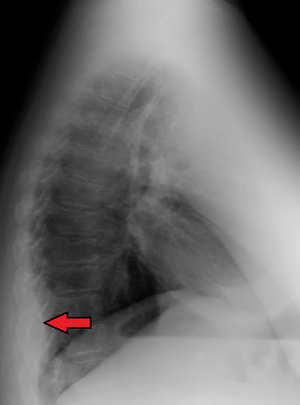

Mediastinal lipomatosis | |